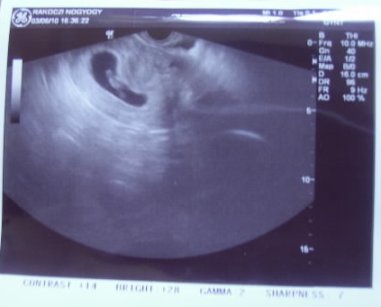

Leti, én még sosem voltam betöltött 12. héten 12. heti uh-n

, hanem 11+4 nap, 11+2 nap.

Genetikai, ahogy majd a 18. heti is az lesz. Most nézik 12. hetin a tarkóredő vastagságát, ami nagyon fontos a Down-szűrés szempontjából. Meg még egy csomó mindent, hogy lássák minden megvan, minden úgy áramlik, ahogy kell és ott van, ahol lennie kell.

Betti, nagyon jó kép. Elhiszem, hogy imádtad hallani a szívverését

Akkor olyan elevennek érzed. Kis kapaszkodó addig, míglen aztán érzed a rugdosást.